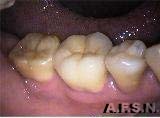

ANTES DEPOIS

Substituição de restaurações em amálgama de prata por resina composta no segundo pré-molar e por ONLAY ARTGLASS no primeiro molar.